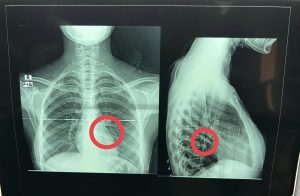

نجح فريق جراحى بقسم جراحة القلب والصدر بمستشفى بنها الجامعي بمحافظة القليوبية، في إنقاذ حياة فتاة تبلغ من العمر حوالي 18 سنة، ابتلعت “دبوس طرحة” عن طريق الخطأ أثناء لبسها للطرحة، واستقر بالرئة، تم عمل جراحة منظار شعب هوائية واستخراج الدبوس دون الحاجة لفتح صدر المريضة.

وكشفت مستشفى بنها الجامعي، بقيادة الدكتور عمرو الدخاخني المدير التنفيذي لمستشفى بنها الجامعي، أنه تم إجراء عملية طارئة لاستخراج دبوس طرحة من القصبة الهوائية اليسرى لفتاة تبلغ من العمر 18 عام، ابتلعته عن طريق الخطأ أثناء لبسها للطرحة ونزل في الرئة.

وبدوره، قال الدكتور محمد الجزار استشاري جراحة القلب والصدر بالمستشفى، أنه تم على الفور إدخال الفتاة لقسم جراحة القلب والصدر، وتم إجراء عملية منظار شعب هوائية صلب، وتم استخراج الدبوس دون الحاجة لفتح صدر المريضة